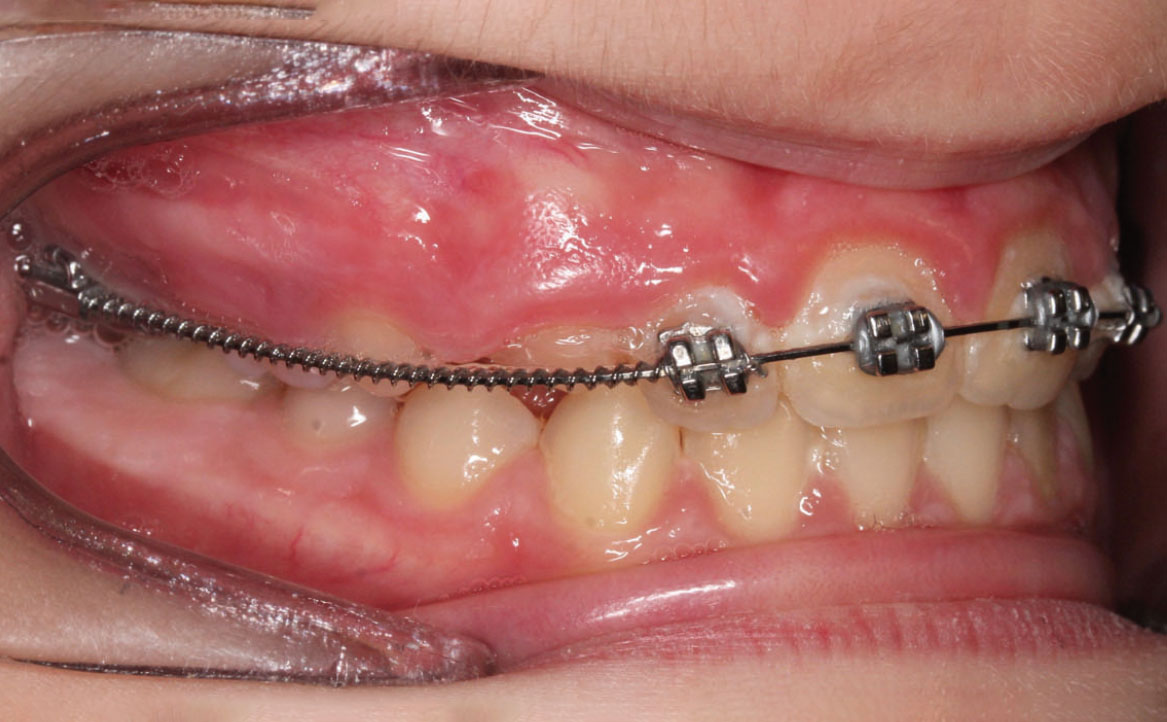

A tre mesi dalla cementazione dell’ERP si programma il bandaggio parziale superiore da 12 a 22 (Mini Master, prescrizione MBT, slot 22×28, American orthodontics) posizionando in maniera strategica i bk su 12 e 22, per il controllo del tip ed evitare interferenza con il tragitto eruttivo di 13 e 23. Sono state posizionate delle open coil attive e arco 016 Tanzo (fig. 8).

Fig. 8A Terapia intercettiva con REP e bandaggio parziale superiore.

Fig. 8B Terapia intercettiva con REP e bandaggio parziale superiore.